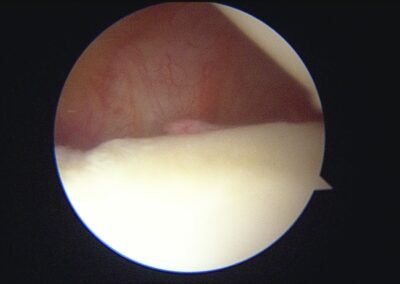

GalleryShoulder rotator cuff repair Meniscus root repair Meniscus repair Bankart repair for recurrent shoulder dislocation ACL reconstruction Machines Instruments